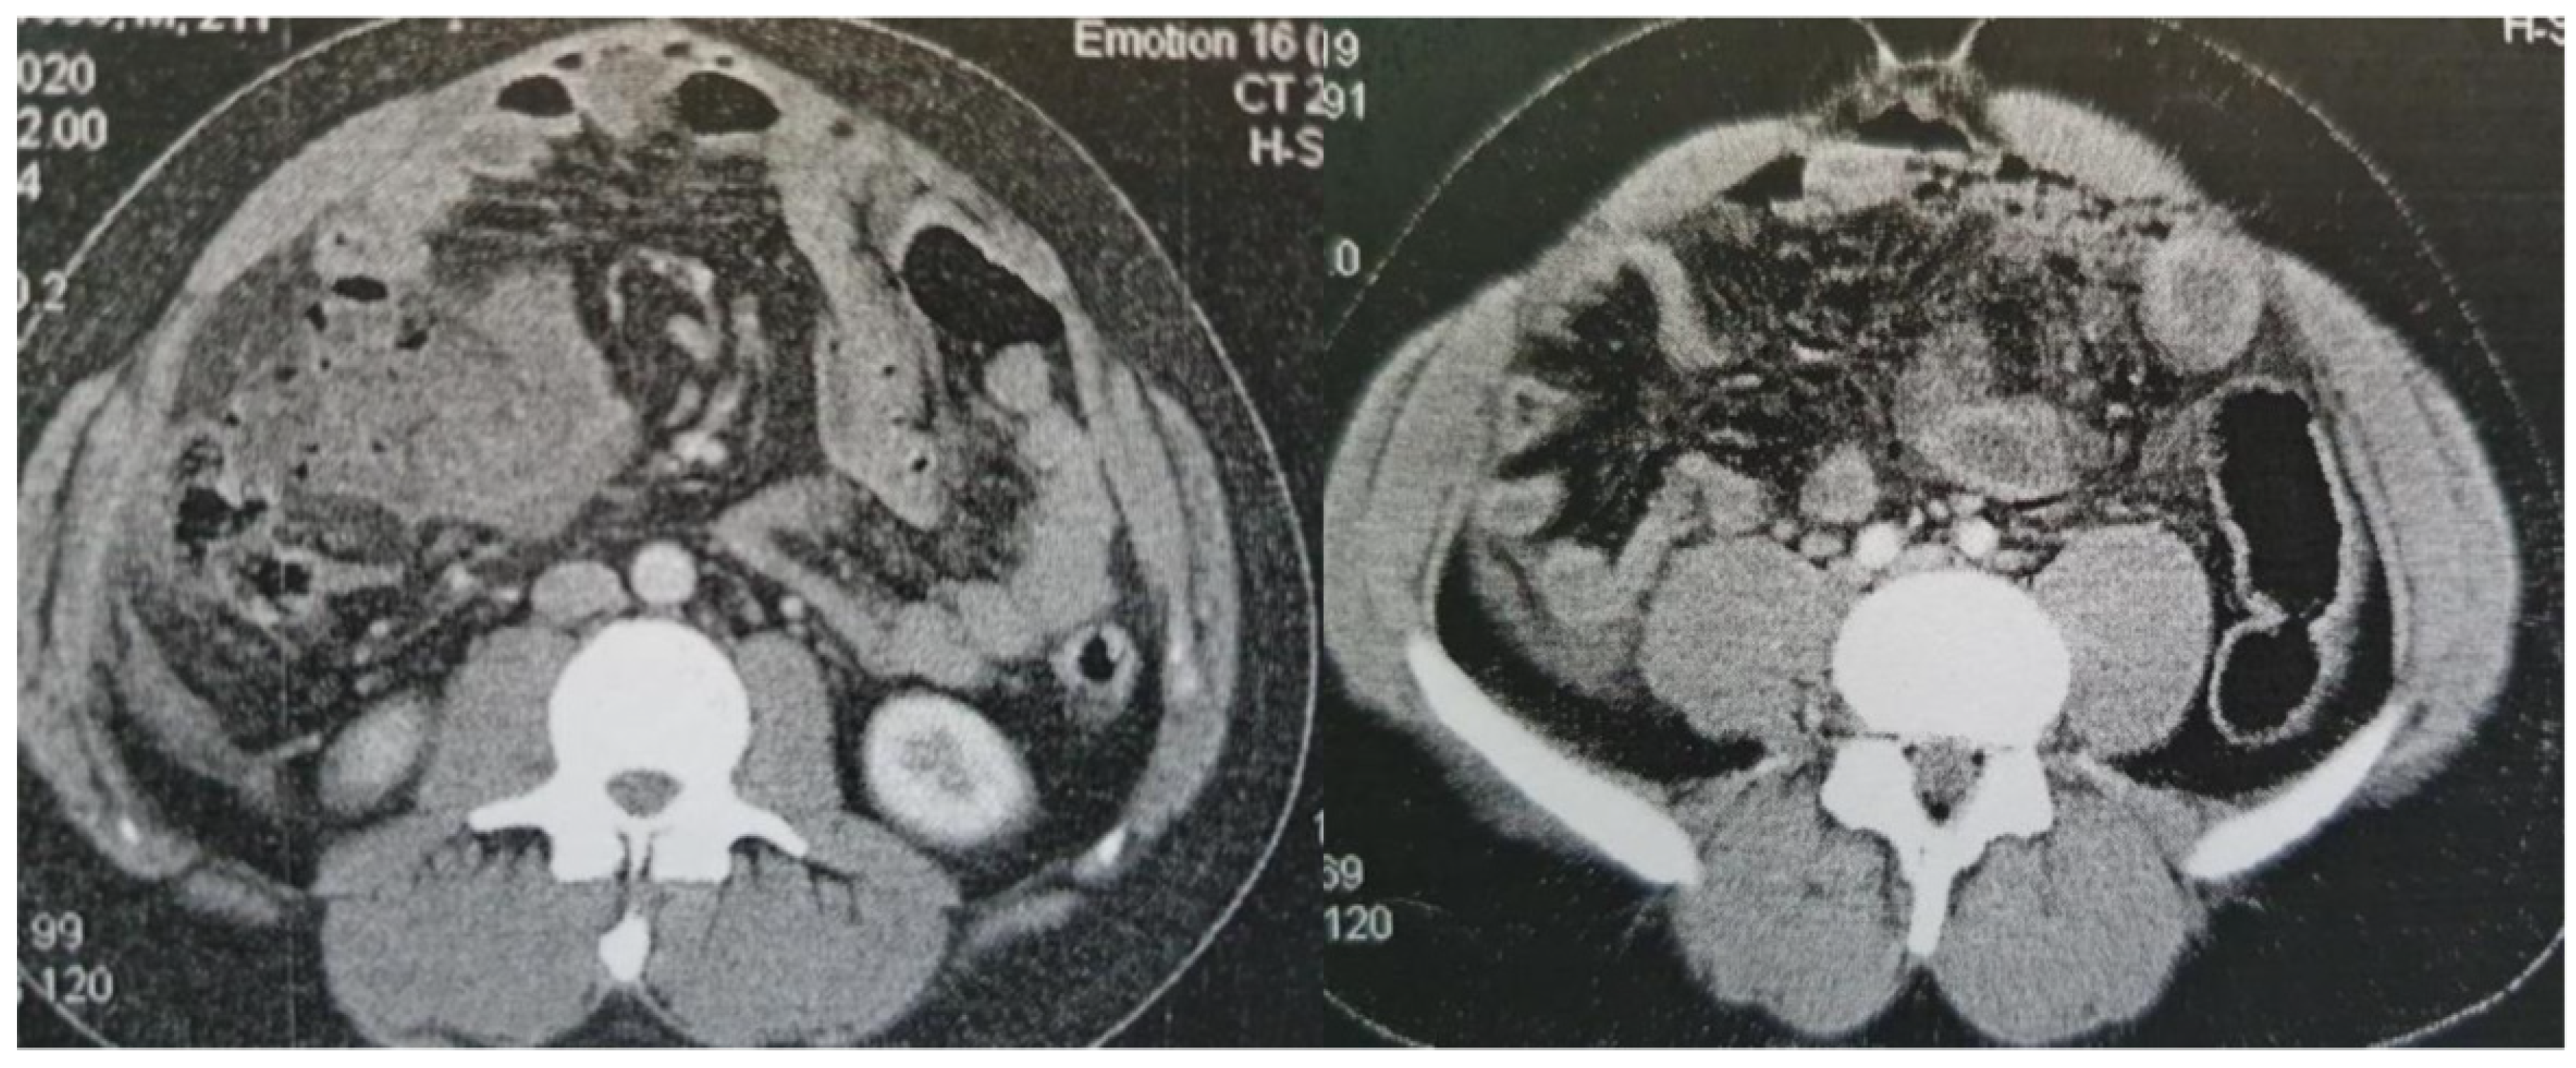

A 23-year-old male was referred to the Surgical department from another hospital for further investigation and management of a high output enterocutaneous fistula and possible short bowel syndrome. The patient’s medical history included several operations in the abdominal cavity due to recurrent incidents of intestinal perforations. His surgical problems had begun two years earlier, when he was admitted to the emergency department with acute epigastric pain, migrating within the next few hours to the right iliac fossa. Laboratory tests revealed leukocytosis (white blood cells (WBC) count 15.32k/μl, neutrophils 87%) and increased C Reactive Protein (CRP) at 1.9mg/dl (normal range: <0.5mg/dl). An abdominal Computed Tomography scan (CT scan) revealed free intra-abdominal air and pneumatosis of the descending and sigmoid colon (Figure 2). Thus, an exploratory laparotomy was performed, revealing generalized fecal peritonitis and a rupture on the antimesenteric wall of the sigmoid colon and confirming the diagnosis of gastrointestinal (GI) tract perforation. The hole was primarily sutured and the patient was discharged from the hospital on the 9th postoperative day, experiencing an uncomplicated postoperative period.

Figure 2. Contrast-enhanced CT findings Axial images of contrast-enhanced CT on presentation (A) and a subsequent episode of perforation (B). In both cases, a note is made of marked fat stranding, free intraperitoneal gas bubbles, and small bowel wall thickening, suggestive of small bowel perforation.

However, four months later the patient presented to the emergency department of another tertiary hospital with acute abdominal pain. A new CT scan showed once again free intra-abdominal air, indicative of small bowel perforation. A third explanatory laparotomy took place. Intraoperatively, perforation of the ileus was observed and therefore a 30cm long enterectomy of the small intestine was performed.